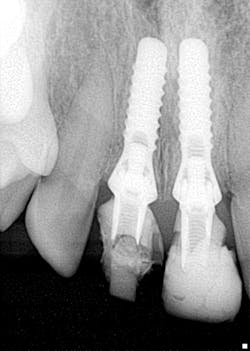

A quick radiographic assessment revealed missing coronal tooth structure/temporary material on No. 8 and rough edges for No. 9 (figure 1). Clinically, the temporary had broken resin on the buccal of the temp coping and was barely hanging on by a thread. Plaque and debris were heavy, accompanied by a fetid odor (figure 2).

Figure 1: Implants 8 and 9 with temps